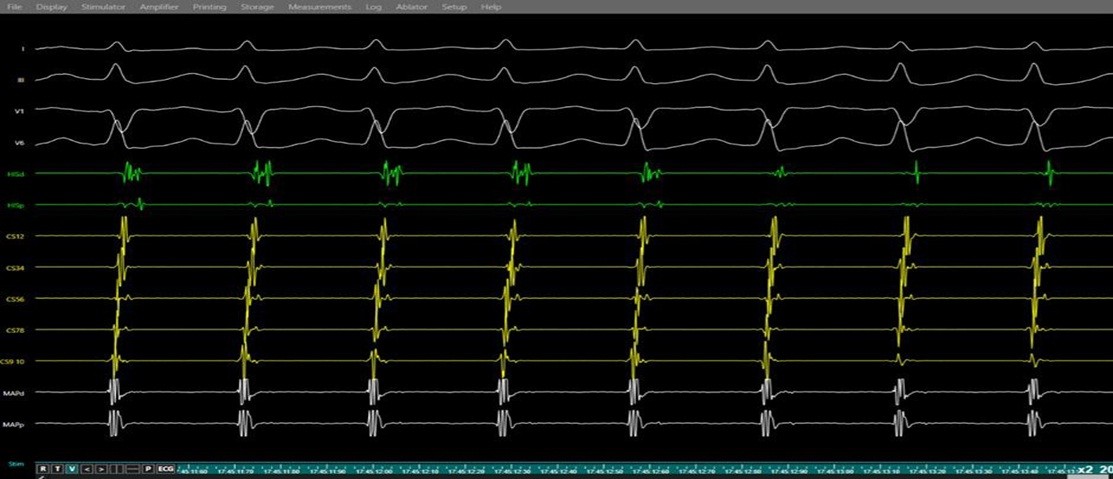

Intracardiac recordings confirmed dual atrioventricular nodal physiology with AH jump. Programmed atrial stimulation (S1S2 400/260 ms) reproducibly induced typical slow-fast AVNRT. Tachycardia diagnosis was validated by ventricular entrainment demonstrating post-pacing interval minus tachycardia cycle length of >115 ms and VAV response. Radiofrequency ablation (45 watts, 55°C, 10 seconds) of slow pathway region produced junctional rhythm confirming correct slow pathway localisation. Further consolidation lesions were applied. Post radiofrequency ablation , no tachycardia was induced despite aggressive PES protocol and isoprenaline suggestive of successful slow pathway ablation. Total procedure duration was 28 minutes with fluoroscopy time of 8.2 minutes (Fig. 7-9). No acute complications occurred.

Figure 9. Junctional rhythm during slow pathway ablation

Simultaneous surface ECG (leads I, II, V1, V6) and intracardiac electrograms (coronary sinus, and ablation catheter) demonstrating junctional rhythm occurring during radiofrequency energy delivery at the slow pathway region a marker of effective slow pathway modification during AVNRT ablation.

AVNRT - atrioventricular nodal re-entrant tachycardia, ECG – electrocardiogram